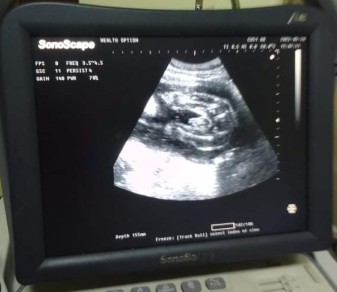

Mga mummy , ano sa tingin nyo ?? Boy or girl ? 💙❤ Sobrang likot nya naging breech position nya , sana umikot pa sya . #27weekand2days #1stimemom #pregnancy

boy po mommy. ganyan din position ni LO ko nung inultrasound ako to check the gender. congrats in advance!

i think boy po. ganyan po ung posisyon ng baby ko and ung sa utz ganyan na ganyan po and boy po sya 😆

mukang boy. parang yung lawit nya yung nakausli eh

baby boy kitang kita c pototoy..hehehe congrats btw sis..❤

boy po 💕 . sken kc girl e. kita ung hiwa 🤗

Boy po tingin ko kc ganyan din sakin may lawit😂